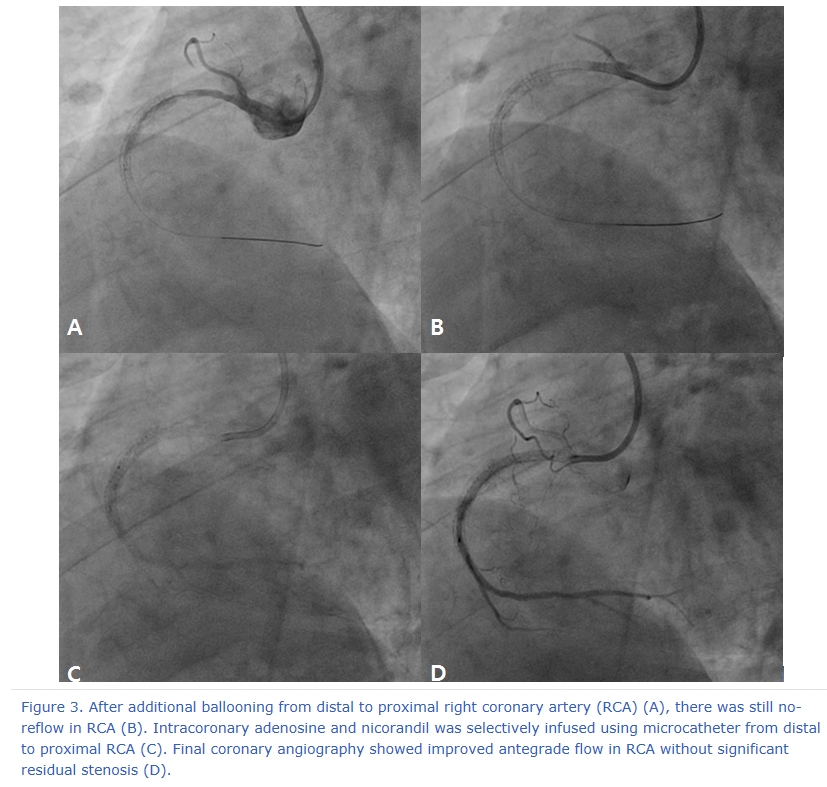

A 78 year-old male visited the outpatient department of Chonnam National University Hospital with intermittent chest pain for 4 months. He underwent percutaneous coronary intervention (PCI) for acute myocardial infarction (AMI) using bare metal stent in the proximal right coronary artery (RCA) 8 years ago. After that, he had undergone repeat intervention using drug eluting ballooning 7 years ago and PCI for mid RCA 6 years ago due to repeated in-stent restenosis (ISR) in RCA. He was treated with dual anti-platelet therapy of aspirin (100 mg daily) and clopidogrel (75 mg daily). Recently, he suffered from chest pain intermittently and was taken to our hospital. The 12-lead electrocardiogram showed normal sinus rhythm and left bundle branch block (no interval change) (Figure 1), and the level of cardiac enzymes were within normal range. He underwent elective coronary angiography (CAG), and it revealed chronic total occlusion in proximal RCA (Type IV ISR) (Figure 2A) with moderate stenosis in proximal left descending artery (LAD). We considered to do staged PCI for proximal LAD. After wiring into RCA with microcatheter backup, stepwise ballooning using 1.5 mm and 2.5 mm diameter balloon was done. Then, a 3.5 x 38 mm everolimus-eluting stent (Xience Alpine®) was implanted at proximal RCA (Figure 2B). Just after stenting with up to 10 atmospheres, no reflow below the lesion site was shown on follow-up CAG (Figure 2C). Coronary blood flow was not restored after intracoronary adenosine, nicorandil and glycoprotein IIb/IIIa inhibitor bolus injection in RCA (Figure 2D). Although we did additional ballooning from distal to proximal RCA again and again (Figure 3A), follow-up CAG showed still no reflow in RCA (Figure 3B). So, we infused intracoronary adenosine and nicoradil using microcatheter from proximal to distal RCA selectively (Figure 3C). Final CAG showed improved antegrade flow (TIMI III) in RCA without significant residual stenosis (Figure 3D). He was transferred to coronary care unit and monitored with anticoagulation for 1 day.

Figure 3. After additional ballooning from distal to proximal right coronary artery (RCA) (A), there was still no-reflow in RCA (B). Intracoronary adenosine and nicorandil was selectively infused using microcatheter from distal to proximal RCA (C). Final coronary angiography showed improved antegrade flow in RCA without significant residual stenosis (D).